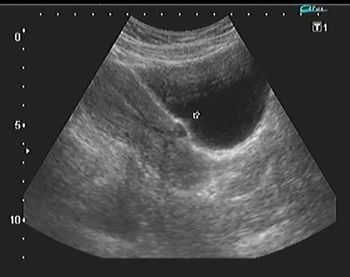

This image quiz focuses on the kidneys. Can you identify the abnormality seen in these ultrasound images of the fetal abdomen?